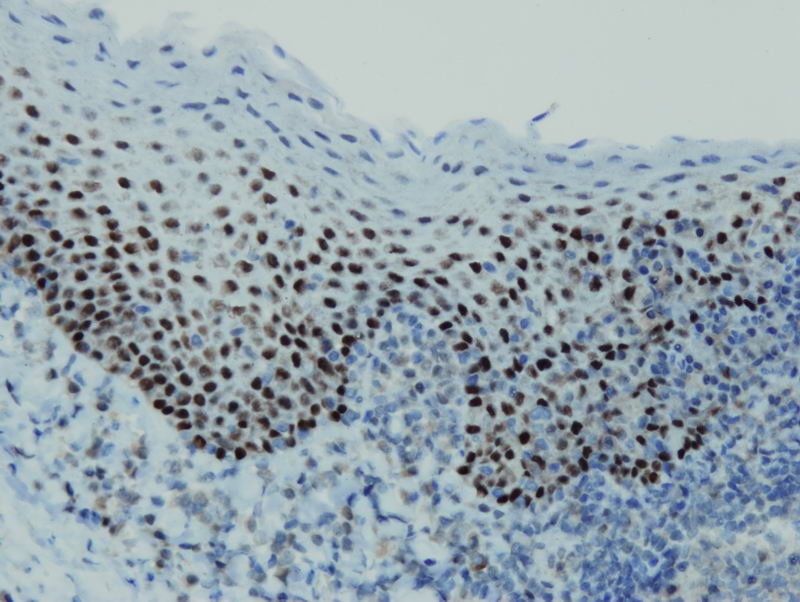

Anti-p63

Peptid derivovaný z internej oblasti ľudského proteínu p63. Protilátka rozpoznáva epitop umiestnený medzi Arg360 - His383.

IHC-P, riedenie 1:100